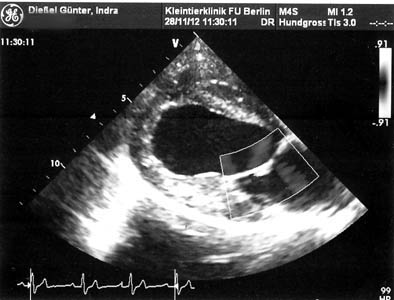

Herzultraschall und Röntgenkontrolle

Beide Methoden werden nur bei Geburtskomplikationen angewendet. Mit dem Herzultraschall kann die Herztätigkeit der Welpen und damit deren Sauerstoffversorgung kontrolliert werden. Durch Röntgen kann die Anzahl der Welpen ermittelt werden. Für beide Methoden steht ein Tierarzt unseres Vertrauens rund um die Uhr zur Verfügung.